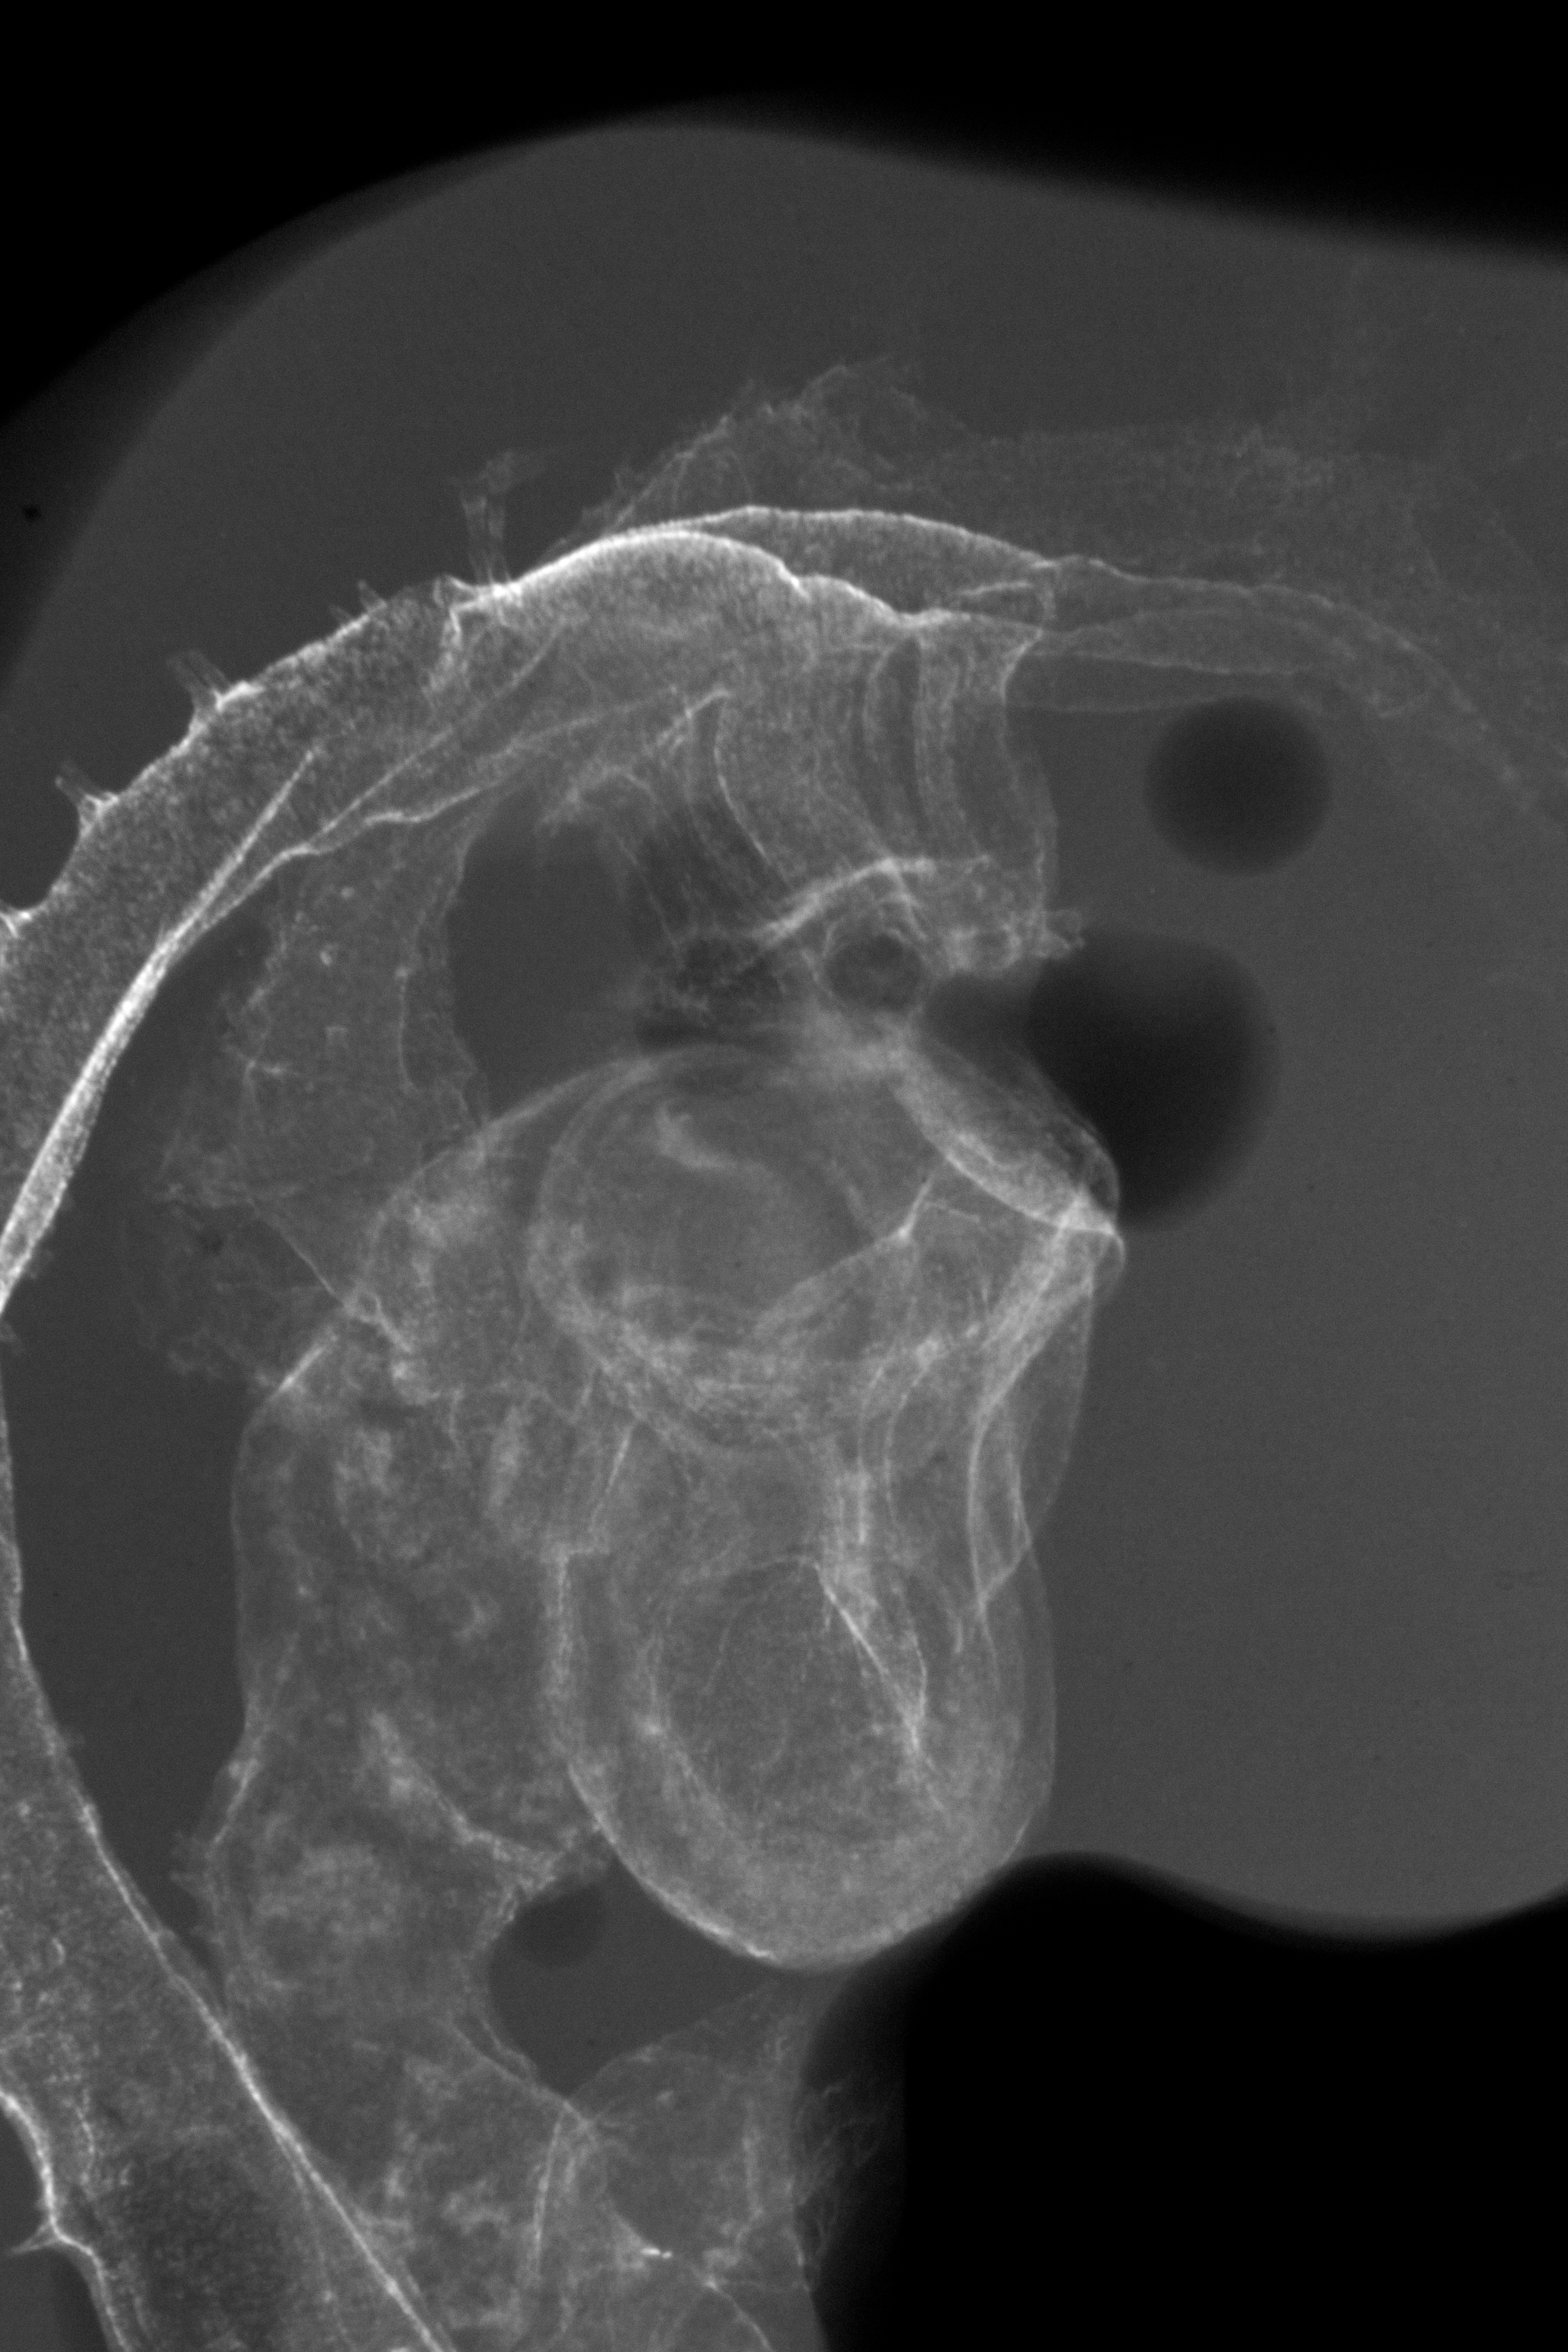

X-Ray Micrographs